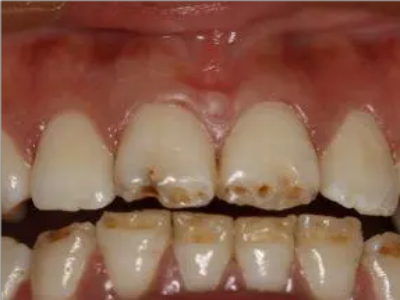

牙釉质发育不全牙齿白斑图

牙釉质发育不全患者可以仅仅出现牙齿色泽和透明度的改变,形成白垩色釉质,即类似于牙齿上有白斑,此时牙冠形态通常较完整。

牙釉质发育不全牙齿上出现白色的斑块图

牙釉质发育不全患者牙釉质表面出现白垩色釉质,表现为牙齿表面色泽不均匀,一般无自觉症状,并且此时牙冠形态较为完整,顶端出现小的缺损。